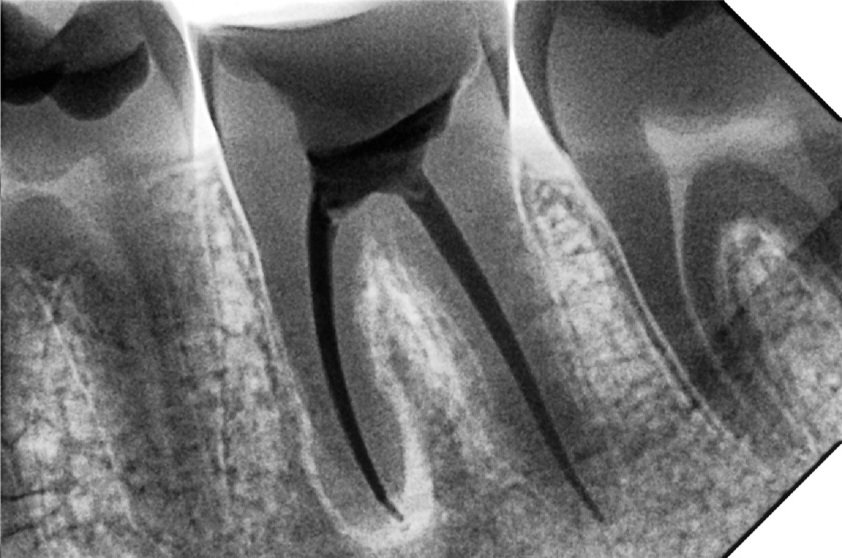

1. Diagnosis & Digital Imaging

Your tooth will be examined clinically and with digital X-rays to determine the extent of infection and the shape of the root canals.